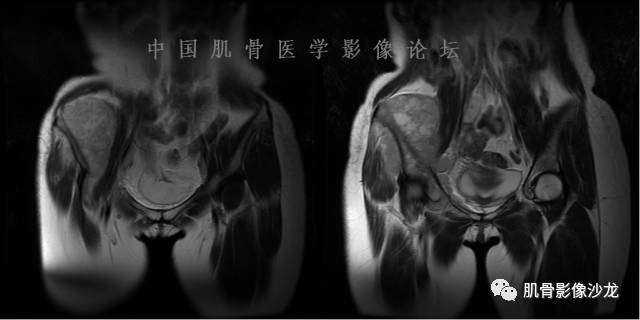

患者2月前无明显诱因下感右腿疼痛、麻木,疼痛呈持续性,发作时无法行走,休息后可缓解。当时无明显肿块,患者遂至当地医院就诊,查X片见右髂骨骨质破坏。6周前患者自觉右髋部渐大肿块,初肿块较小,后肿块逐渐增大,现肿块约12*10cm大小,有压痛。患者遂至我院就诊,查MRI:右髂骨异常信号,伴软组织肿块。ECT、肺CT未见转移。现患者为求进一步治疗,门诊拟“右髂骨肿块 ”收治入院。 患者发病来,神清,精神可,胃纳夜眠可,二便无殊,体重无明显变化。

飞鹰行动 : 第一列可以看见T2小结节样高信号,周围有纤维组织环绕

高回青 : 另外还可以见到扇贝状分叶

1、软骨肉瘤可以有膨胀性骨质破坏(病例3,4),可以有溶骨性骨质破坏(病例2),局部皮质因为破坏变薄,中断 ;

2、软骨基质T2WI高信号,软骨小叶分叶状,也就会出现高老师提到的骨内膜扇贝形压迹。一般认为骨内膜扇贝形压迹超过骨皮质厚度的2/3是软骨肉瘤在长管状骨的特征性表现。如上图。3、软组织肿块或肿胀;